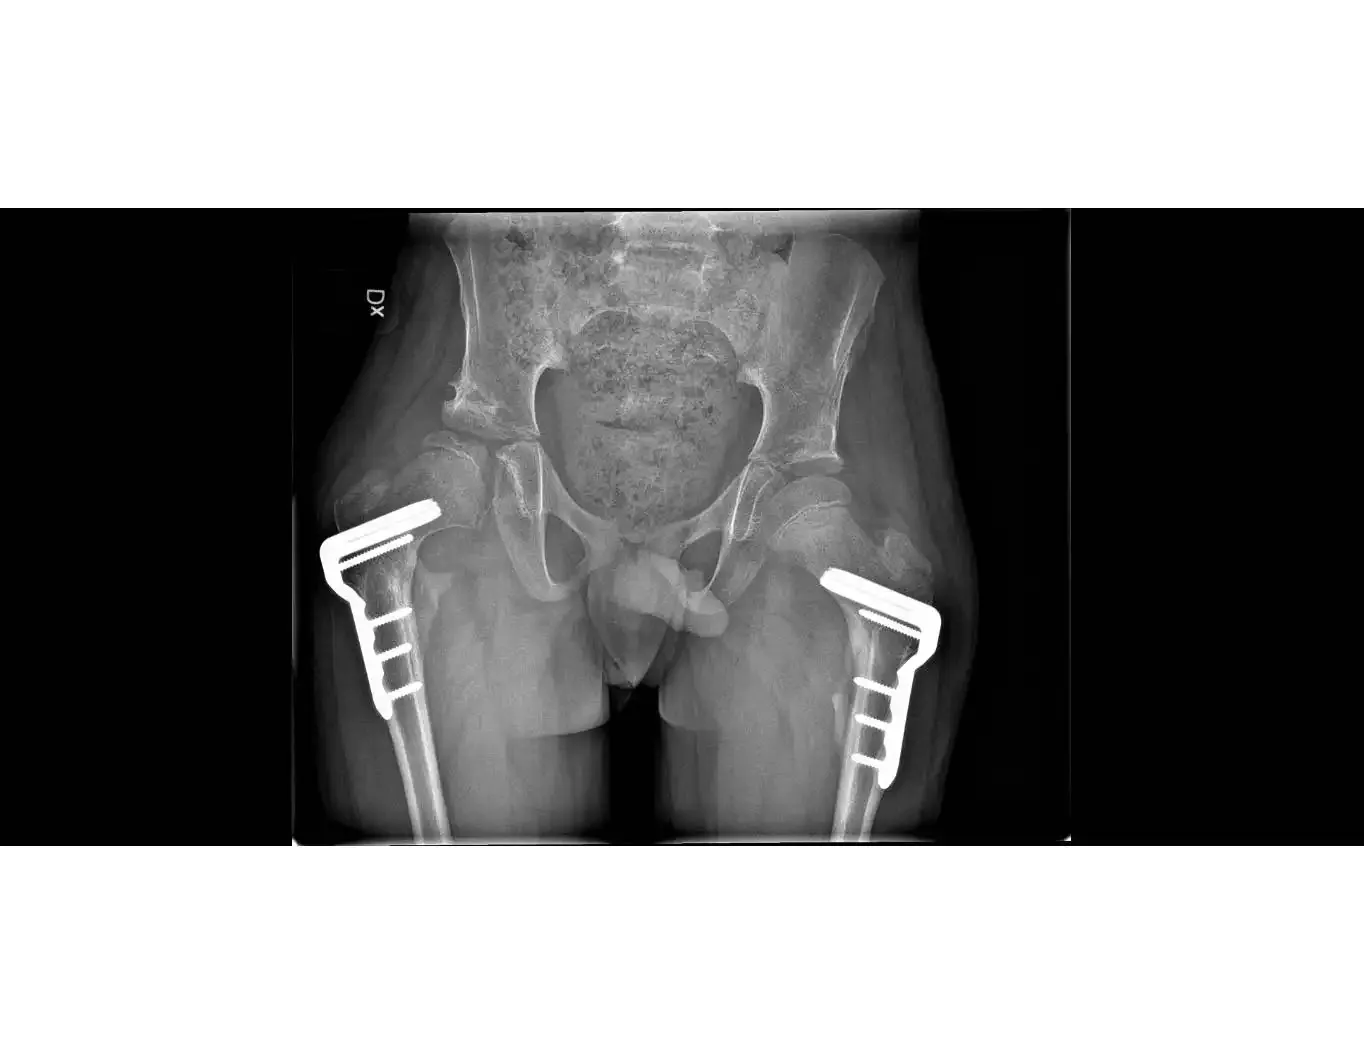

Med vår forskning vill vi öka kunskapen om hur barns utveckling och olika behandlingsinsatser kan påverka livet för barn med diagnosen cerebral pares (CP). Vår forskargrupp har en bred tvärvetenskapligt ansats och är nära kopplad till Neuropediatriska kliniken på Astrid Lindgrens Barnsjukhus, med många internationella samarbetspartners.